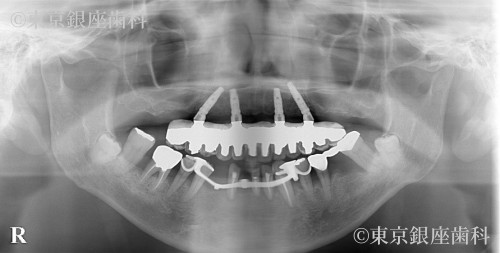

2型糖尿病の治療を経て歯周病の進行によって失われた咬合機能をワンデイインプラントにより回復。ただし費用の都合により上顎のみ手術。患者の希望により残存歯の多い下顎は義歯を使用した例。

After

今回は上顎のみを希望。動揺の激しい残存歯を抜歯、即時にインプラント4本の埋入と仮歯の固定で審美面の回復も行った。

下顎の動揺歯抜歯後の欠損部には作成した義歯を使用。

今回の手術に臨まなければ糖尿病の発見はもっと遅れていた。

2型糖尿病の治療と口腔機能の大幅な改善により全身の健康状態が回復できた。